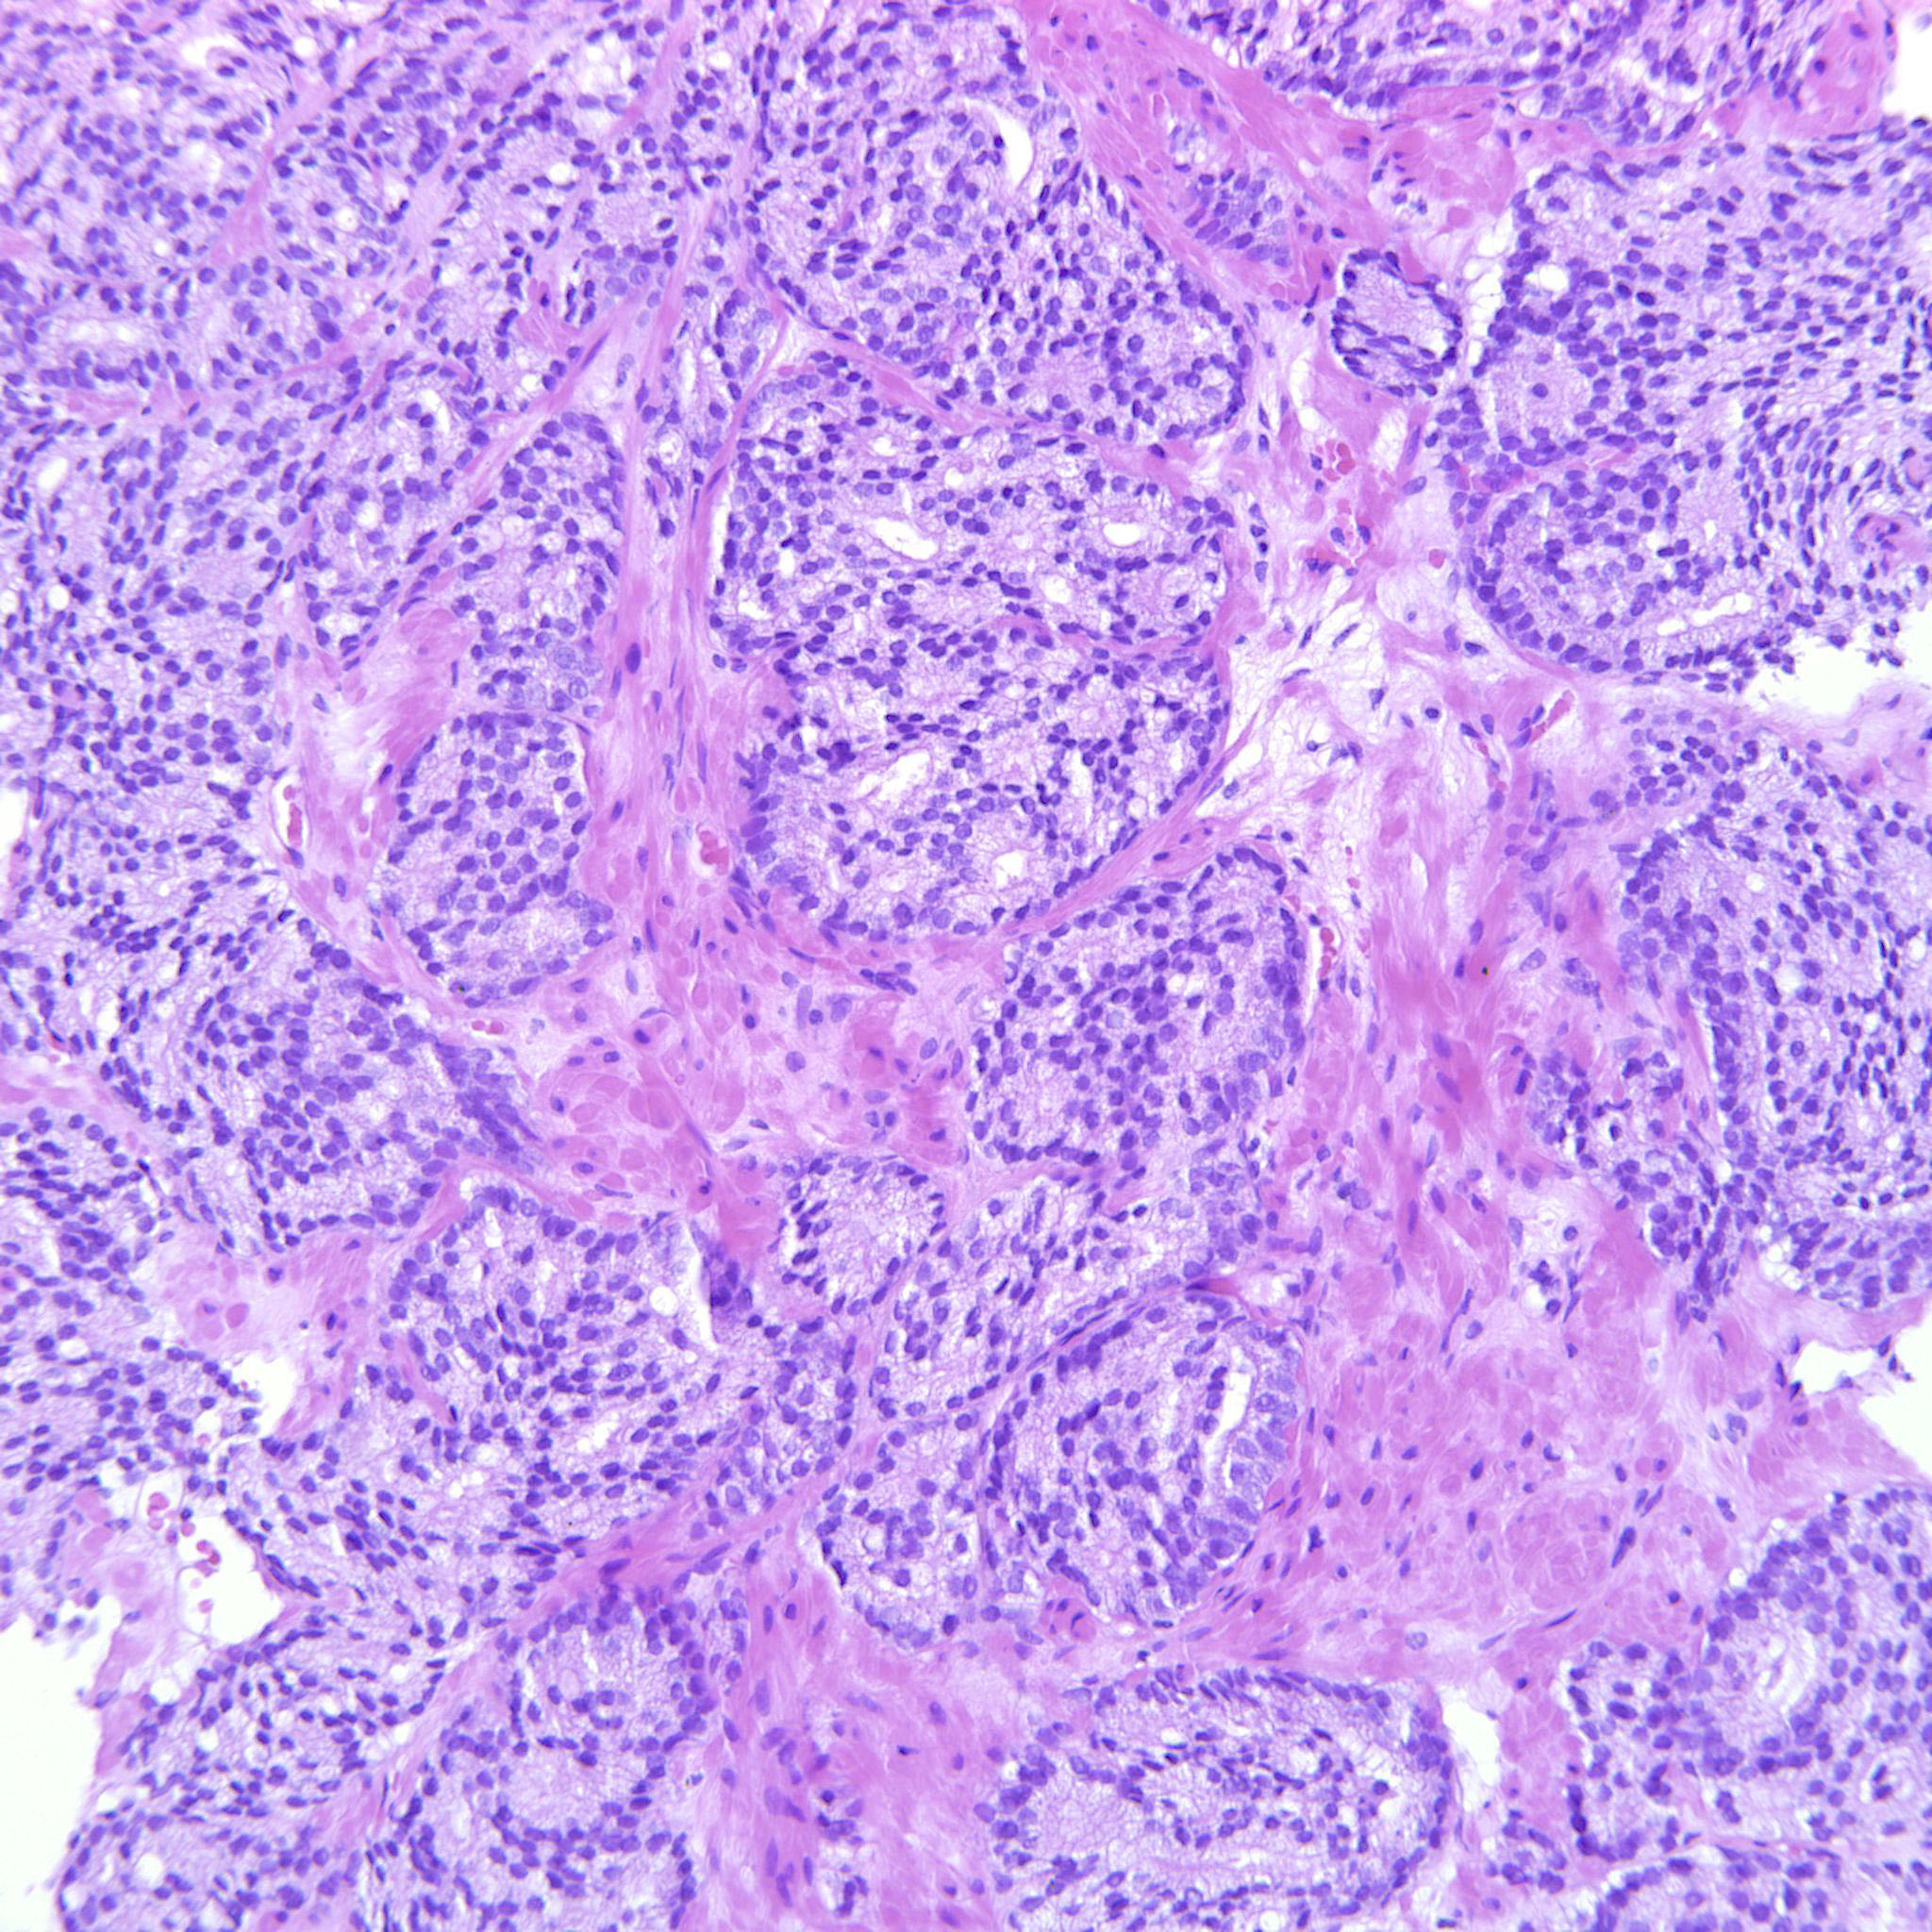

Prostate cancer grading

Case ID: 122